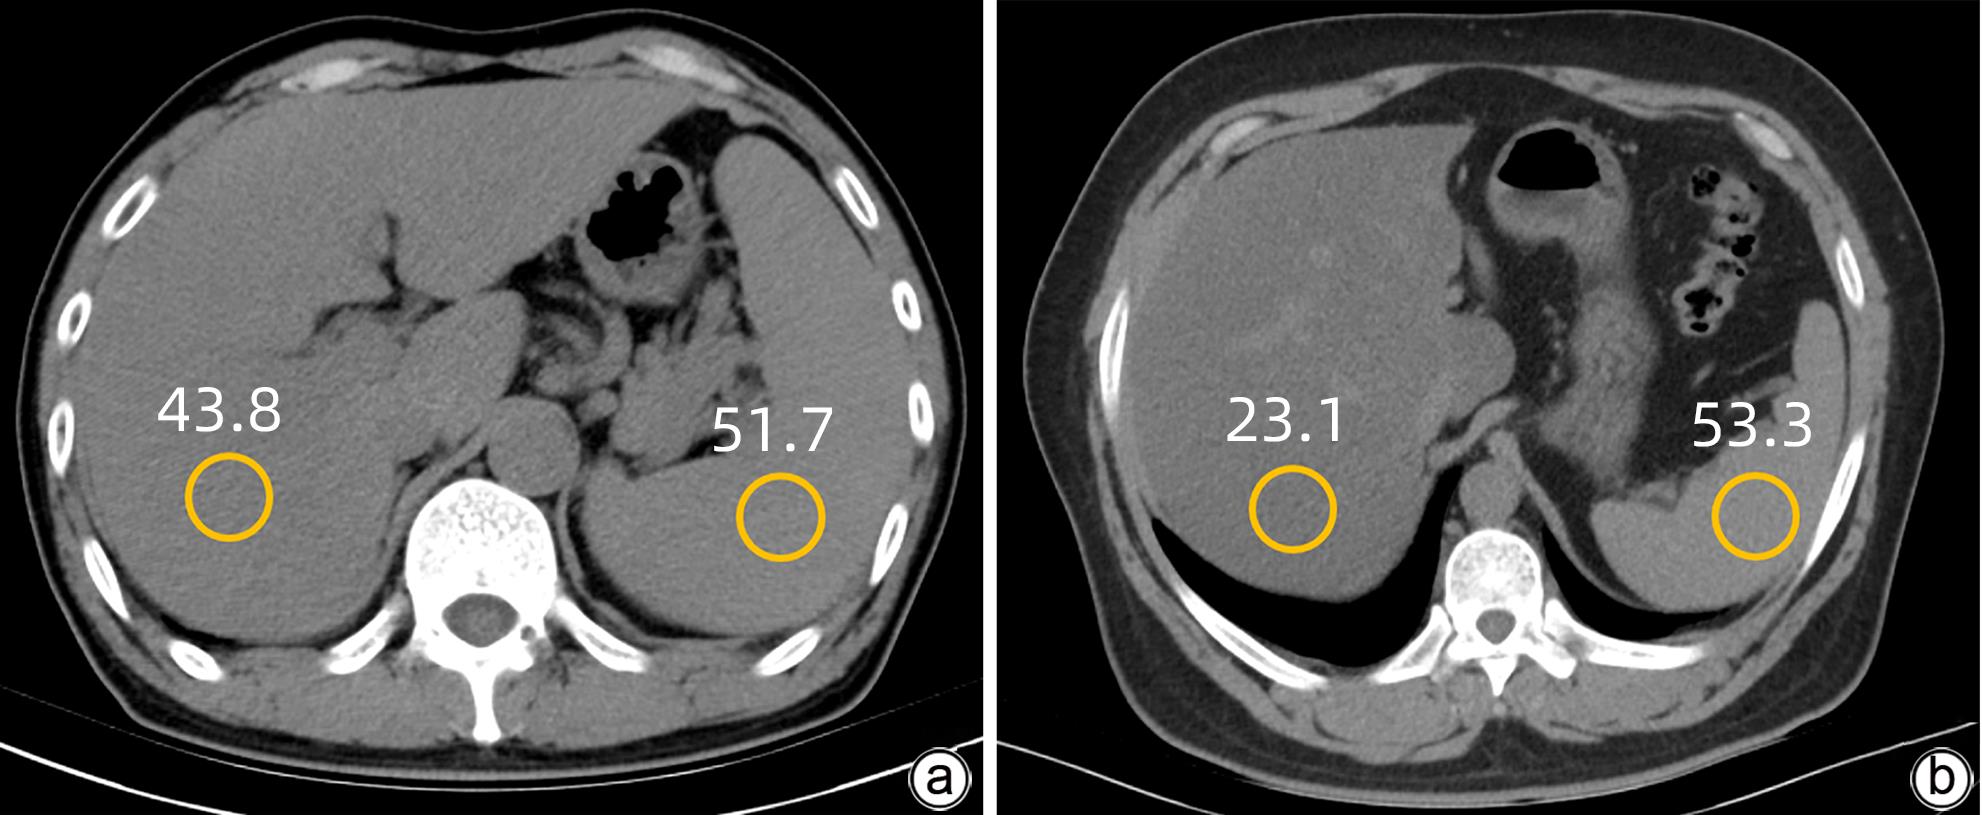

Application value of liver/spleen CT value, controlled attenuation parameter, and magnetic resonance imaging-proton density fat fraction in chronic hepatitis B patients with hepatic steatosis

Jingnan LU, Yansong LI, Ya WEN, Xionghui WANG, Zhaoyu QU, Jianlong LI, Wei ZHANG

2024, 40(1): 46-51. DOI: 10.12449/JCH240109

Objective  To investigate the application value of liver/spleen CT value (CTL/S), controlled attenuation parameter (CAP), and magnetic resonance imaging-proton density fat fraction (MRI-PDFF) in chronic hepatitis B (CHB) patients with hepatic steatosis.  Methods  A retrospective analysis was performed for the clinical data of 213 CHB patients who underwent liver CT, CAP, and MRI-PDFF examinations in Affiliated Hospital of Yan’an University from October 2018 to December 2022. According to MRI-PDFF, the 213 patients were divided into CHB group with 111 patients (MRI-PDFF<5%) and CHB+hepatic steatosis group with 102 patients (MRI-PDFF≥5%), among whom there were 69 patients with mild hepatic steatosis and 33 patients with moderate to severe hepatic steatosis. The independent-samples t test was used for comparison of normally distributed continuous data between groups, and the Mann-Whitney U test was used for comparison of non-normally distributed continuous data between groups. The Bland-Altman plot was used to evaluate the consistency in MRI-PDFF measurement between two physicians. The Spearman’s correlation coefficient was used to analyze the correlation between CTL/S and MRI-PDFF and between CAP and MRI-PDFF. The receiver operating characteristic (ROC) curve was plotted and the area under the ROC curve (AUC) was calculated to investigate the value of CTL/S and CAP in the diagnosis of different degrees of hepatic steatosis, and the DeLong test was used to compare the AUCs of the two radiological examinations.  Results  MRI-PDFF had relatively high repeatability and stability in CHB patients. There is a significant negative correlation between CTL/S and MRI-PDFF (r=-0.800, P<0.001) and a significant positive correlation between CAP and MRI-PDFF (r=0.692, P<0.001). Both CTL/S and CAP had a relatively high accuracy in the diagnosis of hepatic steatosis in CHB patients, with an AUC of 0.951 and 0.902, respectively, and CTL/S had a better accuracy than CAP (P<0.05). In the diagnosis of mild and moderate-to-severe hepatic steatosis, CTL/S had an AUC of 0.921 and 0.895, respectively, and CAP had an AUC of 0.859 and 0.825, respectively, suggesting that CTL/S had a slightly higher diagnostic efficiency than CAP.  Conclusion  MRI-PDFF has high repeatability and stability in CHB patients, and CTL/S and CAP have a high diagnostic value for different degrees of hepatic steatosis in CHB patients.